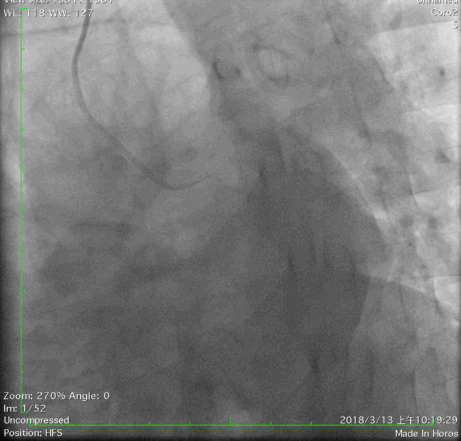

经右股动脉(8F),送EBU 3. 5指引导管指引导管至左冠开口。Sionblue导丝至LCX保护,Finecross 130到达LCX远端待命。Sionblue引导Corsair 135cm微导管进入LAD。近段纤维帽坚硬(伴钙化随后IVUS证实)尝试使用Gaia1st进入前次假腔,导丝升级Gaia 3rd谨慎前进入间隔支S1,推送corsair进入S1交换KDLC,Pilot 200导丝平行进入LAD真腔。Corsair交换Sionblue到LAD远端。IVUS证实全程真腔,闭塞段以纤维为主。植入支架完成血运重建。

G3前进

Pilot扭身进入lad

Pilot200进入真腔